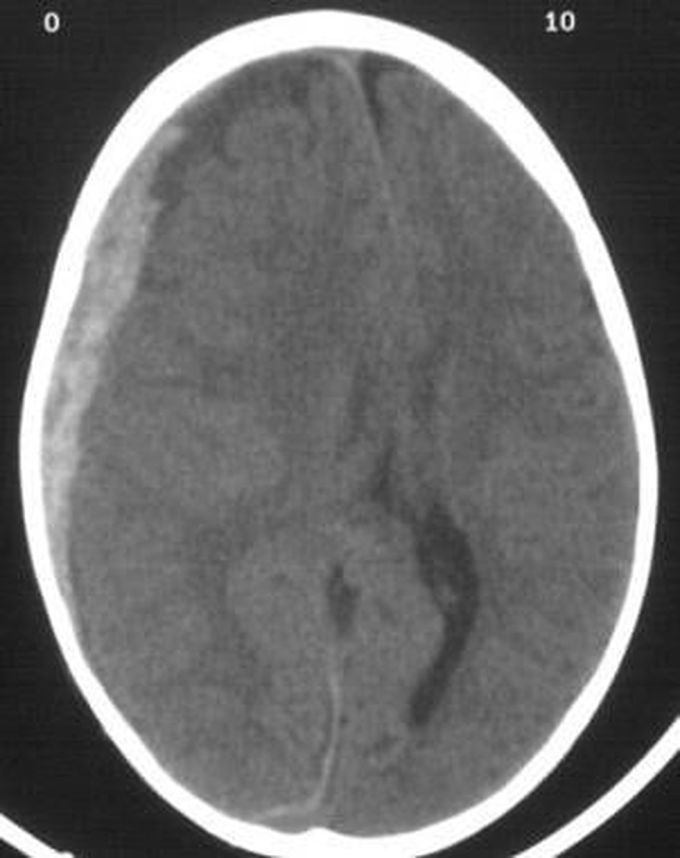

Subdural hematoma Radiopaedia Vitamin K Subdural Hematoma Critical care neurology (kn sheth, section editor) published: Subdural hematoma (sdh) risk and may expand hematoma easily, increase risk of death, have worse outcome. Subdural hematomas are an important bleeding complication of anticoagulation. We quantify the risk of. Treatment of acute subdural hematoma. Background and purpose—subdural hematomas are an important bleeding complication of anticoagulation. We quantify the risk of subdural. Vitamin K Subdural Hematoma.

Image Subdural Hematoma MSD Manual Professional Edition Vitamin K Subdural Hematoma Critical care neurology (kn sheth, section editor) published: Subdural hematoma (sdh) risk and may expand hematoma easily, increase risk of death, have worse outcome. Treatment of acute subdural hematoma. We quantify the risk of subdural hematoma associated with anticoagulation with vitamin k antagonists (vkas) compared with other oral. Subdural hematomas are an important bleeding complication of anticoagulation. Background and purpose—subdural. Vitamin K Subdural Hematoma.

AcuteonChronic Subdural Hemorrhage Due to Late Vitamin K Deficiency Vitamin K Subdural Hematoma Treatment of acute subdural hematoma. Critical care neurology (kn sheth, section editor) published: We quantify the risk of. Background and purpose—subdural hematomas are an important bleeding complication of anticoagulation. Subdural hematoma (sdh) risk and may expand hematoma easily, increase risk of death, have worse outcome. We quantify the risk of subdural hematoma associated with anticoagulation with vitamin k antagonists (vkas). Vitamin K Subdural Hematoma.

AcuteonChronic Subdural Hemorrhage Due to Late Vitamin K Deficiency Vitamin K Subdural Hematoma We quantify the risk of subdural hematoma associated with anticoagulation with vitamin k antagonists (vkas) compared with other oral. Background and purpose—subdural hematomas are an important bleeding complication of anticoagulation. Subdural hematomas are an important bleeding complication of anticoagulation. Critical care neurology (kn sheth, section editor) published: Treatment of acute subdural hematoma. We quantify the risk of. Subdural hematoma (sdh). Vitamin K Subdural Hematoma.